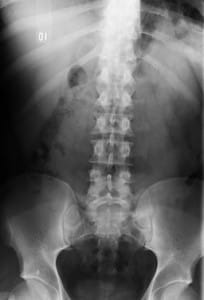

Radiografía